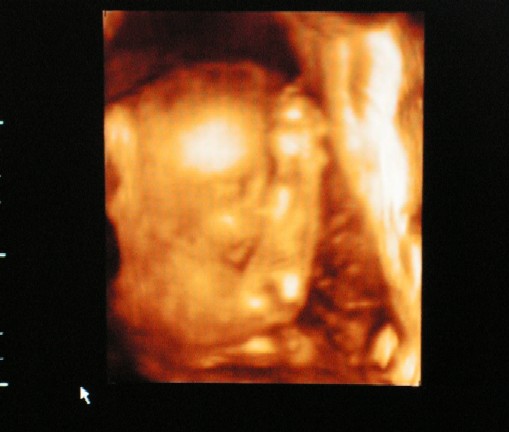

Ez az UH dolog nekem is szöget ütött a fejembe. Az én babám a 4D-n , amikor megpróbálták elcsipni az arcocskáját, állandóan eltakarta magát. Egyfolytában az arca elé tette a kezeit, de csak akkor mikor ott köröztek a feje körül. Még nevettünk is, mondván biztos szégyellős a kicsike, de nincs kizárva, hogy őt is zavarta.

Hát, a mi lányunk is nagy ívben letojta a 4D-t, sajnos abszolút nem sikerült normális képet csinálni a pofijáról. Homályosan kivehetők a vonásai, de nem sikerült úgy, ahogy reméltem. Összekuporodott egy gombócba és a lábaival végig az arca előtt kalimpált, majd egy hatalmasat ásított bele a képünkbe, miután felénk fordult egy pillanatra, szóval lehet abban valami, hogy zavarja a babókat az uh. Doki bácsinál meg állandóan körbe körbe bukfencezett, meg rúgkapált, nem marad nyugton soha. Szerintem útálja az uh-t. :)